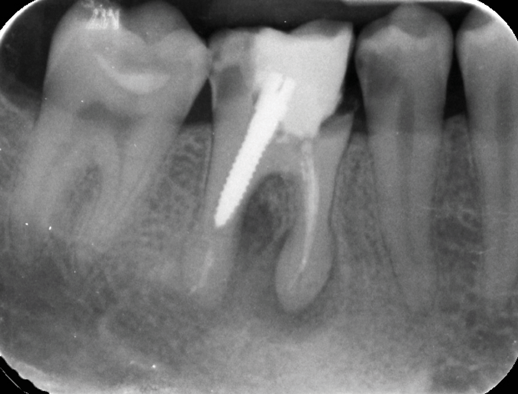

Furthermore, the reconstruction of endodontically treated teeth can present restorative and esthetic challenges for the technician and clinician.23 The failure of these post-retained systems has been documented in numerous clinical studies.10,13,21,24-29 Many of these studies indicate that the failure rate of restorations on pulpless teeth with posts and cores is higher than that for restorations of vital teeth because of their structural differences and the significant loss of tissue.30-35 Several main causes of failure of post-retained restorations have been identified, including recurrent caries, endodontic failure, periodontal disease, post dislodgment, cement failure, post-core separation, crown-core separation, loss of post retention, core fracture, loss of crown retention, post distortion, post fracture, tooth fracture, root perforation (Figure 1), improper post placement (Figure 2), and root fracture.11,36,37Also, corrosion of metal posts has been proposed as a cause of root fracture.38 A post and core system fabricated with dissimilar metals can cause galvanic corrosion that occurs between the two dissimilar materials.39 This gradual destructive process involves the electrical interaction of at least two different metals or nonmetallic conductors in an environment (ie, microleakage) that accelerates the corrosion of at least one of them, while the least noble metal corrodes the most.

Fig 1. Root perforation caused by improper preparation and placement of an oversized post (dentistry courtesy of Riccardo Tonini, MD, DDS).

Figure 1